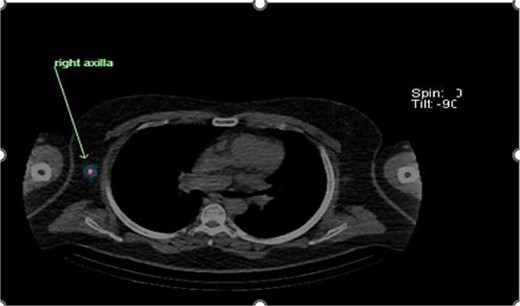

Preoperative lymphoscintigraphy was performed to detect the sentinel lymph node (Fig. 1), expecting it to be in the right inguinal region (Fig. 2). However, drainage to both the right axillary (Fig. 3) and inguinal areas was demonstrated. During surgery, a gamma camera confirmed drainage to both regions (Fig. 4). Blue dye was injected around the previous scar, and sentinel nodes were dissected guided by both blue dye and gamma camera for histopathology.

Unexpected drainage visualized toward the right axillary lymph nodes.